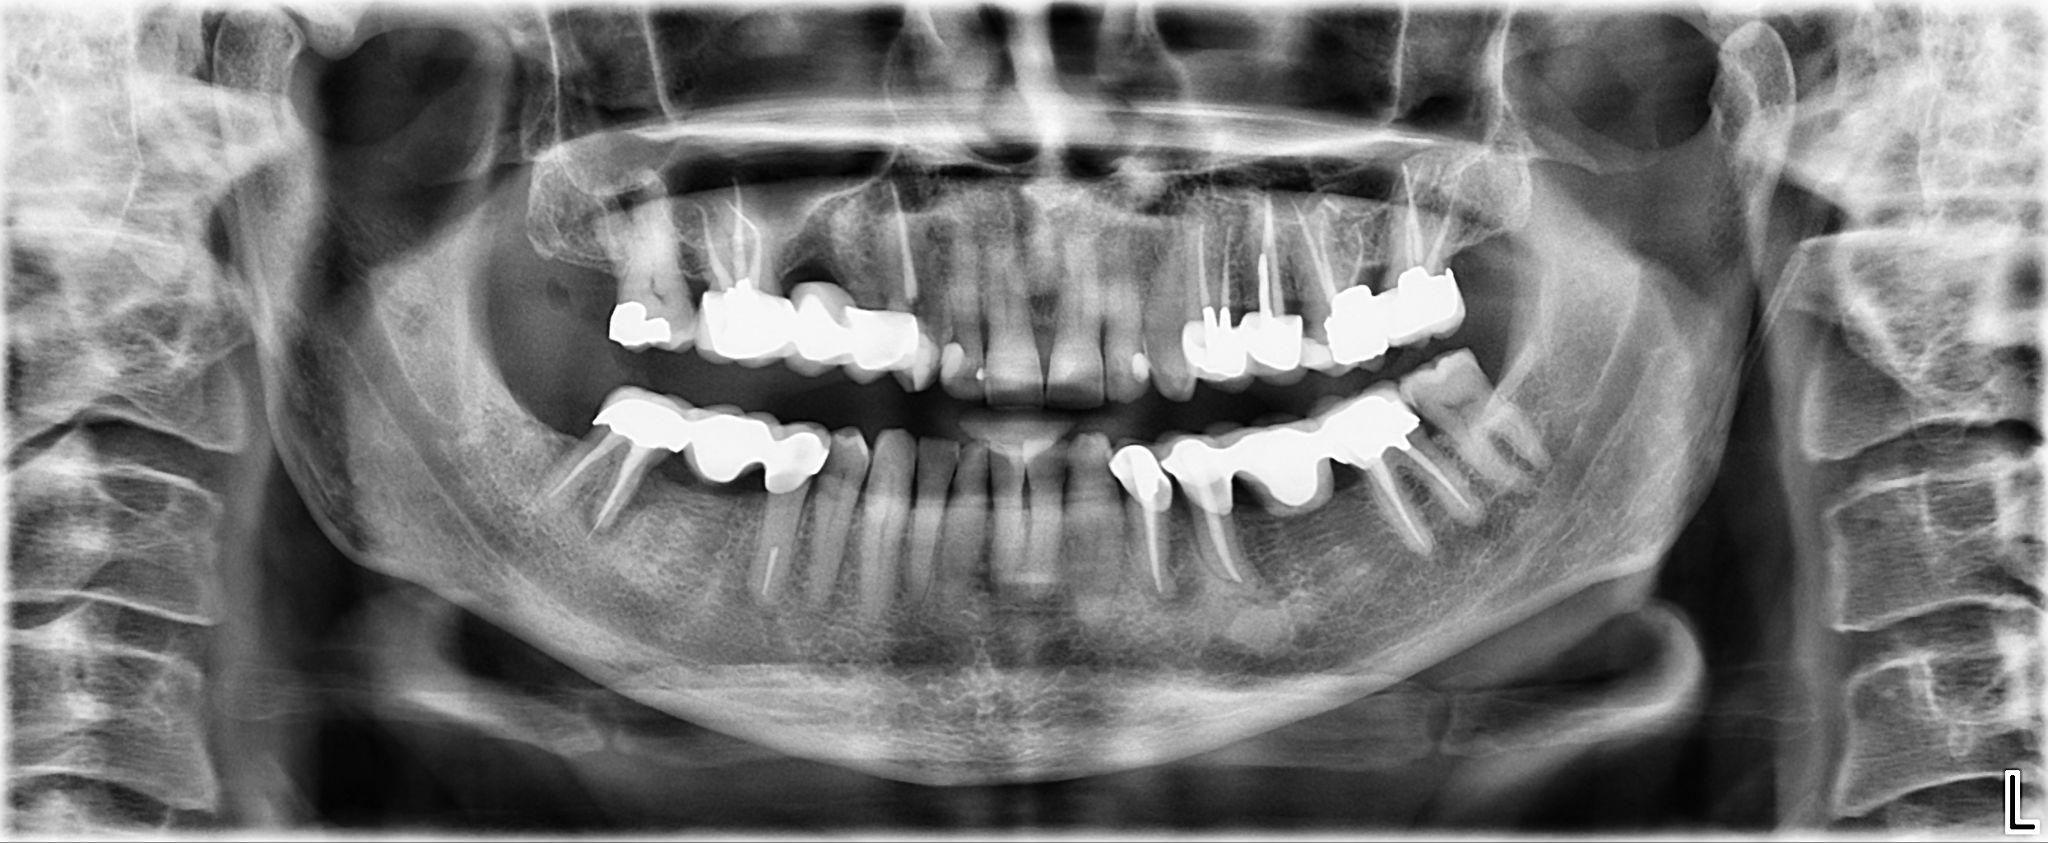

14. What option cannot be selected for the upper jaw of this panoramic X ray?

15 / 25

15. What option cannot be selected for the lower jaw of this panoramic X ray?

16 / 25

16. What option cannot be selected for the upper jaw of this panoramic X ray?

17 / 25

17. What option cannot be selected for the lower jaw of this panoramic X ray?

18 / 25

18. What option cannot be selected for the upper jaw of this panoramic X ray?

19 / 25

19. What option cannot be selected for the lower jaw of this panoramic X ray?

20 / 25

20. What option can be selected for the upper jaw of this panoramic X ray?

21 / 25

21. What option cannot be selected for the lower jaw of this panoramic X ray?

22 / 25

22. What option cannot be selected for the upper jaw of this panoramic X ray?

23 / 25

23. What option cannot be selected for the lower jaw of this panoramic X ray?

24 / 25

24. What option cannot be selected for the upper jaw of this panoramic X ray?

25 / 25

25. What option cannot be selected for the lower jaw of this panoramic X ray?